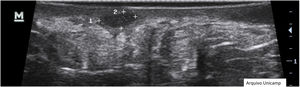

Changes in dermal thickness and echogenicity (Fig. 5).

Anechoic or hypoechoic dermal pseudocysts – round or oval hypoechoic and anechoic structures in the dermis and/or hypodermis measuring <1 cm, which may clinically correspond to nodules or abscesses (Fig. 6).

Anechoic fluid collections with echoes (debris) – hypoechoic or anechoic dermal fluid and/or hypodermic sac-like structure connected to the base of the enlarged hair follicle, clinically corresponding to an abscess or fistula (Fig. 7).

Hypoechoic fistula/fistulous tracts in the dermis and subcutaneous tissue – dermal or hypodermal hypoechoic or anechoic band-like structure connected to the base of an enlarged hair follicle (Fig. 8).